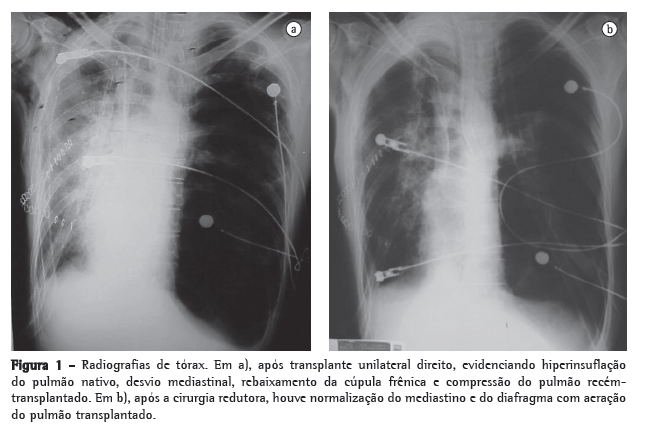

Após 7 meses em lista de espera, foi submetido a transplante pulmonar unilateral direito, com tempo de isquemia de 210 min. A imunossupressão foi realizada com azatioprina, ciclosporina e solumedrol. O paciente foi encaminhado para a UTI, permanecendo intubado por 5 dias. Porém, evoluiu com insuficiência respiratória, necessitando reintubação. Progressivamente, notou-se hiperinsuflação do pulmão nativo, com desvio do mediastino e piora do padrão ventilatório. Optou-se pela ventilação independente, mas não houve melhora radiológica ou clínica (Figura 1).

Foi submetido à cirurgia de redução do volume pulmonar à esquerda para suprimir o efeito compressivo sobre o pulmão transplantado, através da utilização de grampeador linear cortante e múltiplas ressecções em cunha, removendo-se aproximadamente 20% do parênquima do ápice pulmonar. Utilizou-se reforço da sutura mecânica através da interposição de membranas de pericárdio bovino, conforme descrito previamente por Cooper.(8)

Houve melhora radiológica, com expansão do pulmão transplantado e normalização do contorno diafragmático, além de melhora das funções pulmonares (Figura 1). Porém, evoluiu com deiscência da anastomose da parede posterior do brônquio principal direito e fístula broncopleural. Apresentou empiema e quadro séptico, falecendo 16 dias após o transplante.